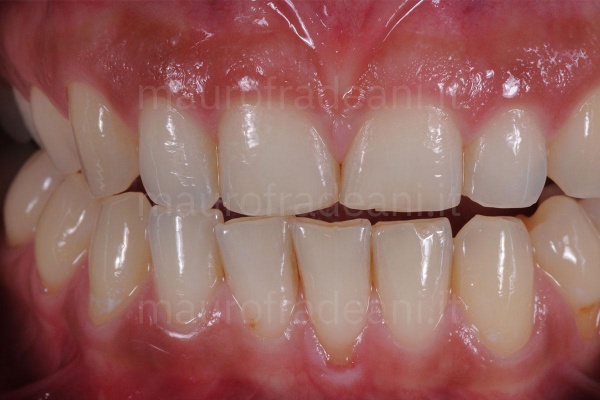

6/6: Front view at the end of the orthodontic treatment: both the misalignment and the initial dental crowding have been fixed.